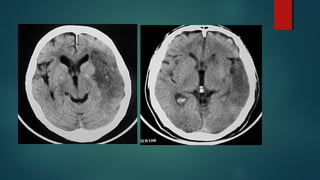

Este documento es el programa para un taller de imágenes del curso de emergencia 2015 impartido por el Dr. Víctor Delgado. El taller se centra en el uso de imágenes médicas para el diagnóstico y tratamiento de pacientes en coma traumático según la base de datos de Marshall. El Dr. Delgado es el único instructor repetido a lo largo del documento.